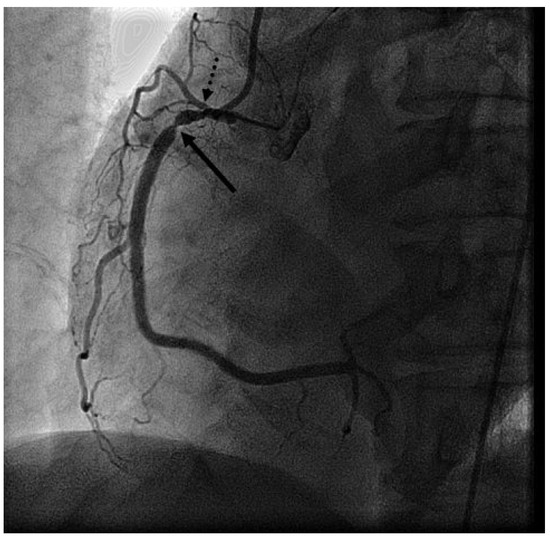

Case Report

Early Morning Recurrent Chest Pain

by Silke Maile, Igal Moarof and Marc Michot

Abstract

The differential diagnosis of recurrent chest pain is manifold. Although it is unlikely in younger people, a cardiac origin should always be considered. We report a case of recurrent chest pain which was initially considered to have a gastrointestinal or psychic origin. A [...] Read more.

The differential diagnosis of recurrent chest pain is manifold. Although it is unlikely in younger people, a cardiac origin should always be considered. We report a case of recurrent chest pain which was initially considered to have a gastrointestinal or psychic origin. A circadian pattern of the pain was conspicuous. Finally, coronary angiography performed in the setting of an acute coronary syndrome followed by life-threatening rhythm disturbances established the diagnosis. Full article

Show Figures

Figure 1